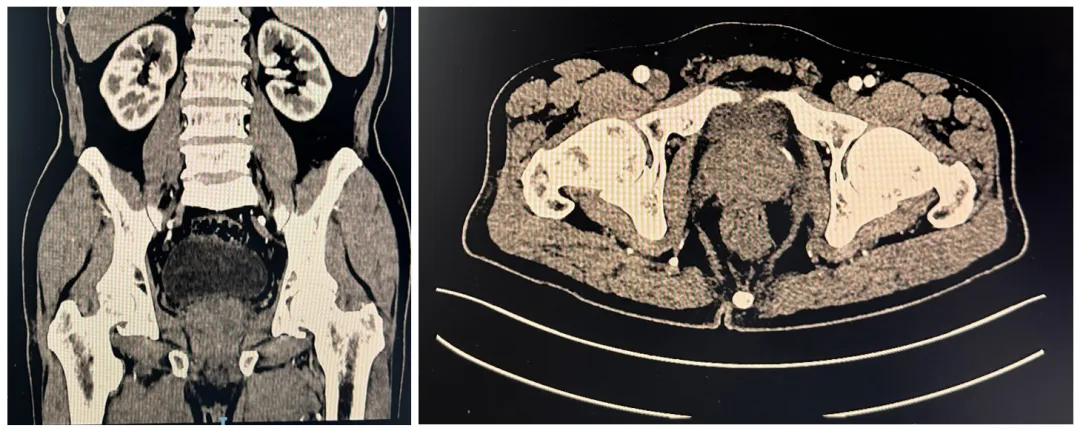

胸部+全腹部增强CT(2024-9-11)

3.png

1.前列腺稍大,强化欠均匀,请结合临床相关检查分析。2.左侧髂骨高密度影,转移?3.右肺中下叶斑片影,考虑感染,建议治疗后复查。4.右肺少许小结节,年度复查。5.气管内附壁黏液栓。6.肝囊肿;左肾结石;左肾上腺瘤可能。7.主动脉管壁少许钙化。